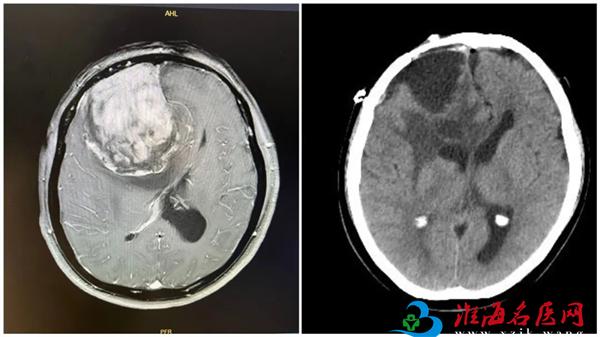

术前术后影像图对比

近日,徐州市中心医院神经外科何晓光团队,运用显微镜与神经内镜“双镜联合”的微创手术技术,成功为一名患者切除颅内肿瘤(大小约55mm×70mm×73mm)。术后患者恢复良好,已顺利出院。

患者王女士(化名),59岁。约1年前,家人察觉其性格变得急躁易怒。7个月前,开始出现记忆力减退、反应迟钝、嗜睡等症状。入院前一周,上述症状加重,并出现行走不稳。当地医院头颅磁共振检查提示:右侧额叶巨大占位性病变,考虑恶性肿瘤,并已引发明显的颅内压增高及脑疝倾向,病情危重。

经详细检查,确定患者肿瘤位于右侧额叶,体积大,且位置关键,毗邻控制肢体运动的脑功能区(中央前回)及重要的大脑引流静脉(上矢状窦)。